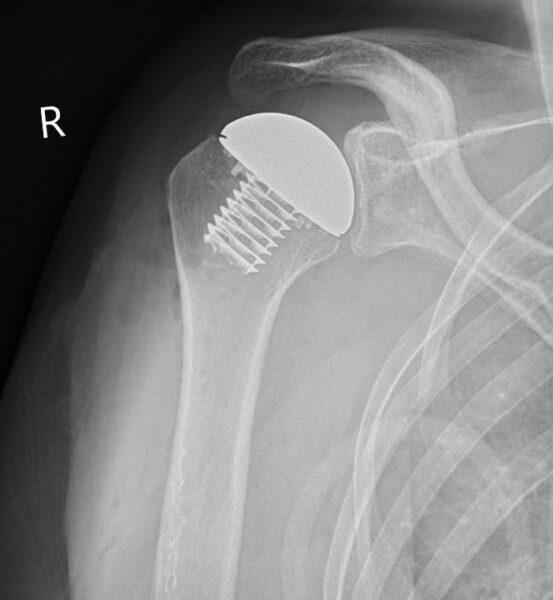

Totale schouderprothese

Is de schouder versleten, maar zijn de spieren en pezen (rotator cuff) nog in goede staat? Dan plaatsen we een totale schouderprothese. Bij een totale schouderprothese vervangen we de schouderkop en de kom van het schouderblad.